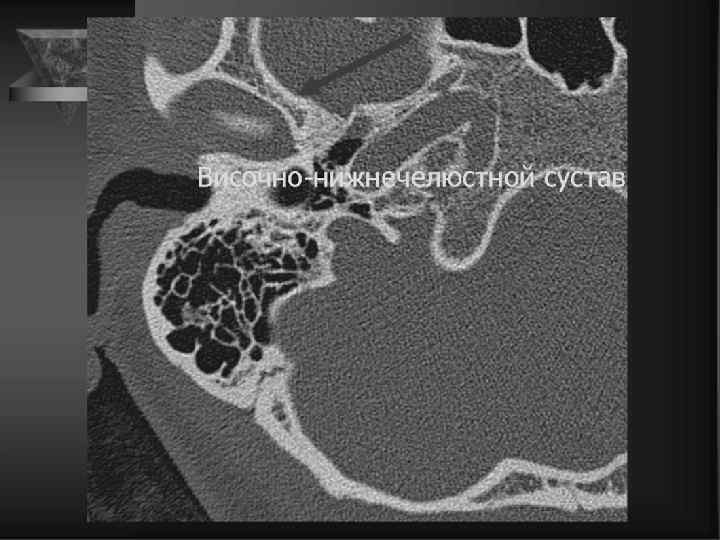

1 ушная раковина 2 чешуйчатые клетки 3 угол Чителли 4 периантральные клетки 5 борозда сигмовидного синуса 6 передний край пирамиды 7 пещера сосцевидного отростка 8 височно-нижнечелюстной сустав 9 краевые клетки 10 головка нижней челюсти 11 скуловой отросток височной кости 12 дугообразное возвышение 13 заднелицевые клетки 14 внутренний и наружный слуховой канал 15 верхушка пирамиды 16 пневматические клетки сосцевидного отростка 17 шиловидный отросток

9 внутренний слуховой проход 10 антрум 1 клиновидно – чешуйчатый шов 2 внутренний затылочный выступ 11 клиновиднокаменистая 3 внутренний затылочный гребень борозда 12 преддверие 4 поддугообразная ямка 13 улитка 5 дугообразное возвышение 14 латеральный полукружный 6 крыша барабанной полости канал 7 верхушка пирамиды 15 барабанная полость 8 передний полукружный канал 16 головка нижней челюсти